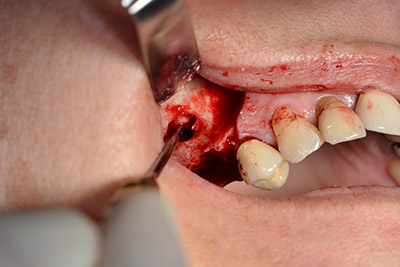

El guiado clásico del corte (crestal, descarga bucal) y la preparación del colgajo mucoperióstico permiten obtener una buena visión global.

En este caso se utilizan implantes Sky (Bredent), cuyo protocolo quirúrgico exige el fresado piloto a unas 1.200 rpm (figura 9).